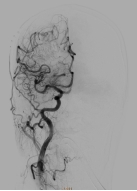

经过周密计划及充分准备,神经外科团队在复合手术室为患者行脑动静脉畸形栓塞术,术中造影提示:大脑前中后动脉、颈外动脉多重供血,引流静脉粗大并形成深部静脉瘤,按照史氏脑血管畸形分级为4级,也就是最高级别的脑血管畸形。造影后,先行栓塞畸形血管团的主要供应血管:右侧大脑后动脉,因血流量大先在血管畸形内填塞三枚弹簧圈,再通过微导管注入液体栓塞剂,成功将畸形血管团大部栓塞。

△介入栓塞后,行右侧颈总动脉造影提示畸形团明显缩小,供血动脉减少